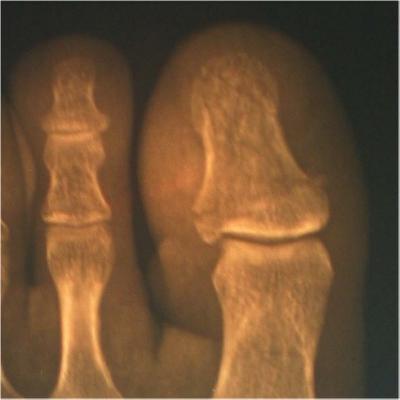

Examination by emergency medical people at a local hospital revealed the diver has a broken toe (comminuted fracture of the left first digital phalange). Basically, the toe was crushed into multiple fragments. Fortunately, this transverse fracture required no pinning or surgery. This type of fracture tends to heal rather well, but this diver missed diving for eight weeks while his body repaired the damage.

The X-rays below of the injury to the diver's left foot show multiple breaks (fine lines) at the in the first bone  (upper right of oblique view) of the big toe

X-Rays of Comminuted Fracture Caused By A Falling Scuba Cylinder

Oblique View

Enlarged Oblique View